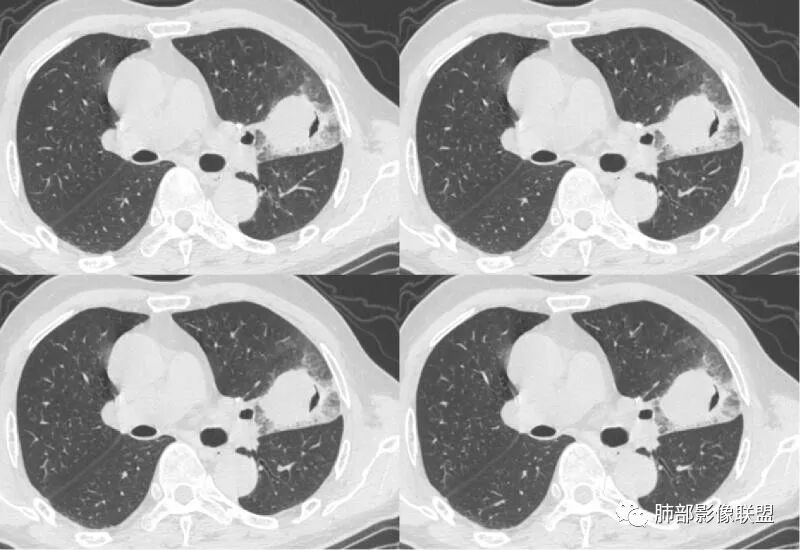

胸膜下实变,周围伴磨玻璃影,长轴与胸膜平行

病灶沿叶间胸膜向内,支气管远端不畅,近端有扩张,所以符合外朝内病变。

我标示一下,尖后段搭到一部分,前段也占了一点点。

主体在舌段

有,斜裂局部膨隆

边缘膨隆,叶间裂有局部膨出下坠

有膨隆+收缩

实变为主,加周围模糊GGO

GGO+实变

支气管?

宇宙星空:

堵塞

尘缘:

支气管外面堵了,近端有扩张

有堵塞,有狭窄

中远端堵塞,堵塞端圆钝

炎性? 肺炎型肺癌待排

1、团片状,实行密度区外观整体圆顿,位于上叶尖后段与下舌段区间。局部膨隆,但未见分叶,肿瘤多见。

4、支气管改变:上舌段支气管远段延入部分稍示僵硬。尖后段见分支支气管阻塞,恶性多见。

5、周围磨玻璃,3个月后逐渐转为密实,应符合当初附壁生长为主,且逐渐向实体成分转换。

6、病变长轴平行且受限于胸膜,外围大内带小,符合外朝内发展病变。“腔内结节状明显强化”加之支气管改变有力支持新生物诊断。如此大范围边界不清的磨玻璃影让人浮想联翩。如此大范围病灶,肺门纵隔未见肿大淋巴结也让人意外。